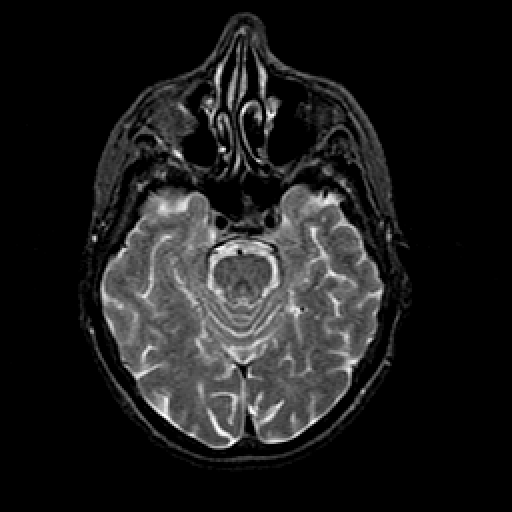

T2-weighted structural MR: Slice 18

Slice 18